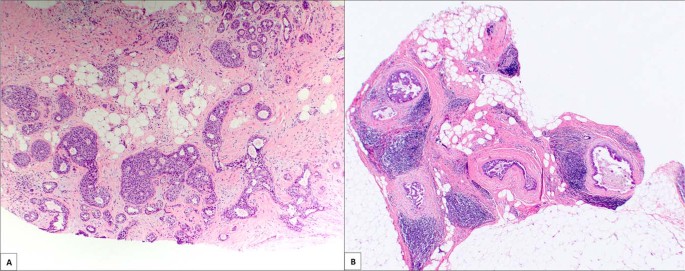

The 20 cases of DCIS had similarities to the invasive carcinomas. The majority were low to intermediate nuclear grade (11/20; 60%) and ER-positive (18/20; 90%) (Table 2). In 70% of the cases, the DCIS involved either a sclerosing lesion or a papilloma (Fig. 3A). In other cases, the DCIS was associated with dense periductal fibrosis (Fig. 3B). All cases were excised; three were upgraded to invasive carcinoma (microinvasive (<0.1 cm), 0.2 cm, and 0.3 cm), and the remaining 17 showed residual DCIS on excision. The DCIS tended to be extensive as the average number of blocks involved on excision was 12 and ranged from 4 to 38 blocks. This translates into an average area of involvement measuring ~4–5 cm11.

All the studies of AD have shown that DCIS makes up a small subset of carcinomas (Table 4). In this study, only 11% of carcinomas were DCIS. The majority (16/20; 80%) were associated with calcifications microscopically, but calcifications were only detected mammographically in six cases (38%). Three were upgraded to small invasive carcinomas on excision (microinvasive, 0.2 cm, and 0.3 cm). The majority of the cases were associated with a sclerosing lesion or a papilloma (65%). The underlying lesion likely contributed to the appearance of AD. In the remaining cases, periductal fibrosis may have played a role. A previous study of five cases of DCIS presenting as AD showed similar results with 2 cases associated with sclerosing adenosis and 3 with dense surrounding stroma20.